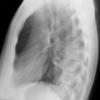

Case 3 RM & UL pneum PA

Date: 07/04/2004

Views: 5551